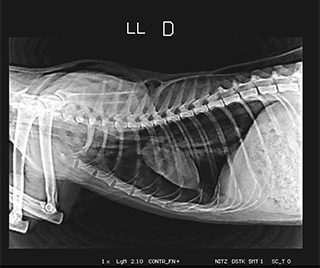

Radiologia Digital Direta / Digital Radiography

As radiografias geradas digitalmente podem ser transmitidas para iPad Apple®, notebooks e smartphones.

iPad com tela Retina Apple® possibilita a visualização das imagens com maior qualidade diagnóstica.

O treinamento aborda a geração das radiografias, a edição digital das imagens, e também a

escolha adequada de técnicas radiográficas como kilovoltagem, corrente elétrica e tempo de exposição.